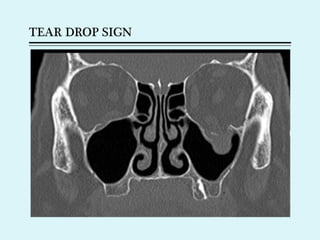

Orbital floor #

 Accompanied by Lefort II and zygoma #s

 Includes ‘Blow out fractures’ ( isolated fractures of orbital floor

when large object strikes the globe- orbital contents herniate

into maxillary antrum- “tear drop sign”)

 Clinical features

 Ecchymosis, enophthalmos, diplopia, hypoasethesia and anaesthesia of

cheek

 Diagnosis

 CT PNS, Water’s

 Traction test- nerve entrapment

 Treatment

 Indication – enophthalmos & persistent diplopia

 Transantal approach

 Infraorbital approach

 Reforcement of orbital floor

TEAR DROP SIGN